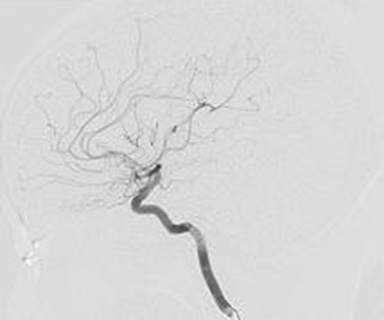

正常な脳血管(動脈)

脳血管造影検査

脳へ流入する血管は4本(左右それぞれの頸動脈・椎骨動脈)あります。

この検査では脳への血管が狭くなっているか、動脈瘤(血管のコブ)があるか、脳出血や脳腫瘍などの周辺に重要な血管があるか、異常な血管があるかなどを調べます。